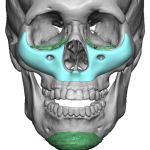

“Aesthetic temporal reduction” (often called temporal narrowing surgery) is a niche craniofacial procedure aimed at reducing the width of the head in the temple region (the area above and slightly behind the eyes). What it targets The temporal region (sides of the skull) Specifically: Temporal bone (outer skull) Temporalis muscle (a chewing muscle that can add bulk) How it’s done Read More…